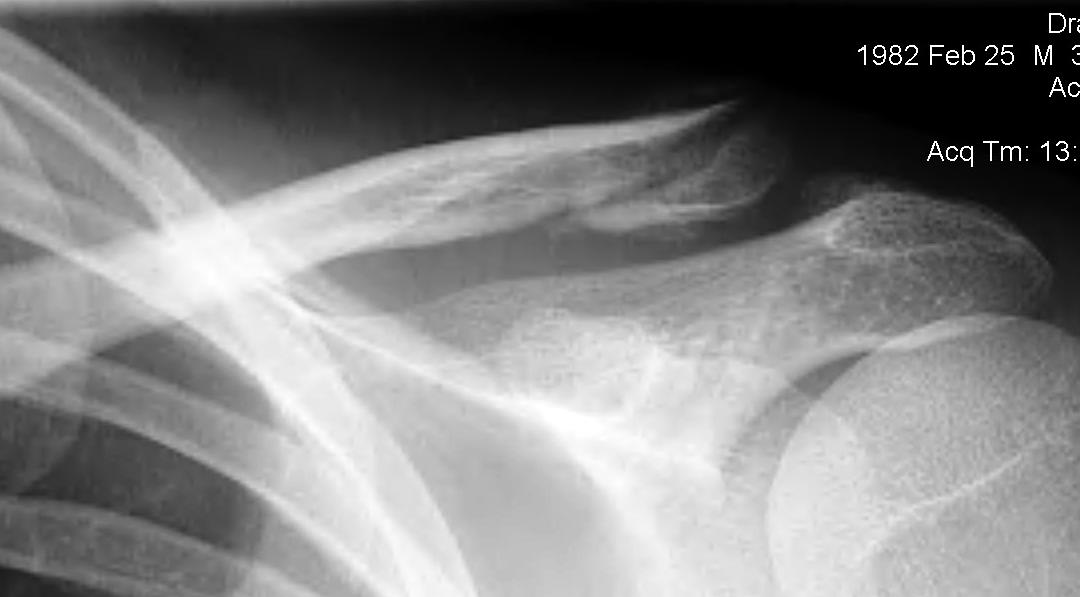

Neer Classification

Fracture lateral to the CC ligaments Non displaced

Fracture medial to the CC ligaments CCL ligaments attached to lateral fragment Medial fragment displaced superiorly |

Between conoid and trapezoid Conoid disrupted Trapezoid remains attached to the lateral fragment |

Lateral to CC ligaments Intra-articular extension Stable |

Periosteal sleeve disruption Pediatric Medial fragment displaced |

Comminuted Type II Medial fragment displaced |

Type I

Type II

Type V